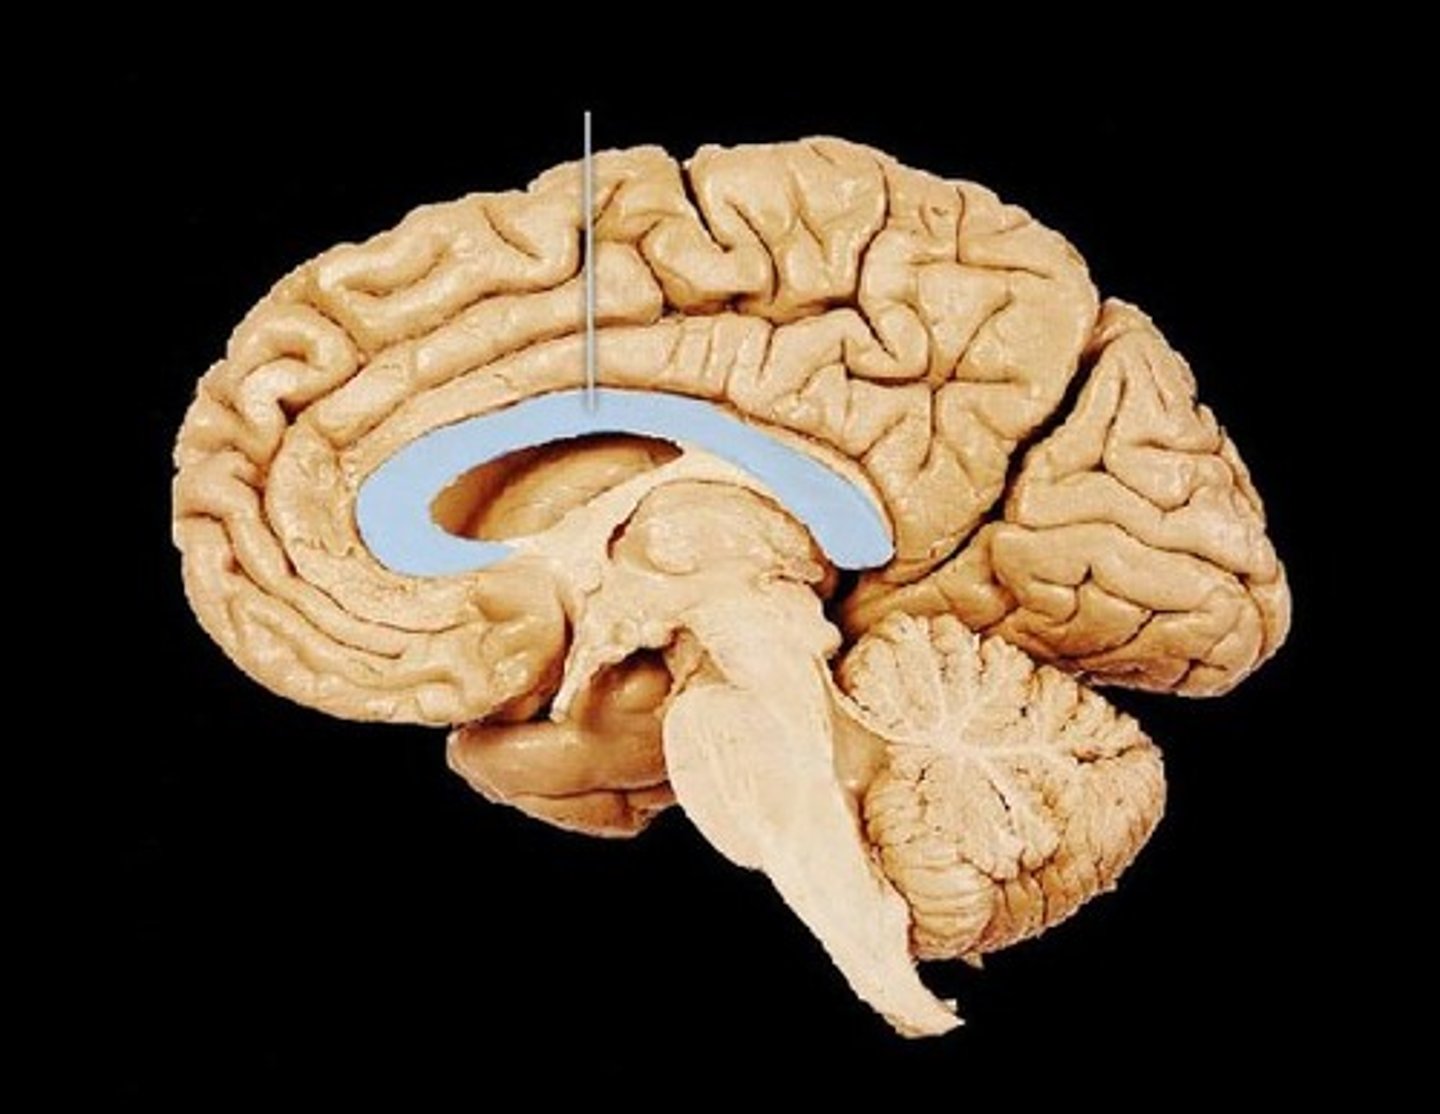

Corpus Callosum

What is this?